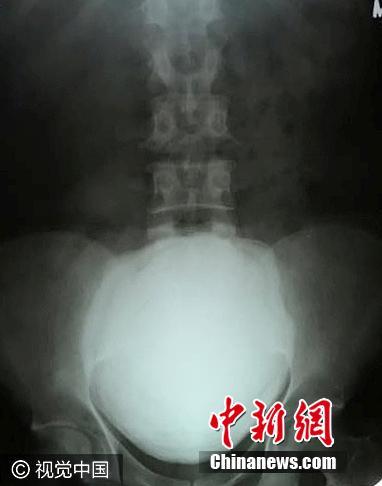

印度男子腹痛入院 膀胱取出1.5公斤巨型結(jié)石

近日,印度古吉拉特邦瓦爾薩德縣,49歲的Maheshbhai Rasikbhai Patel因腹部劇痛入院,醫(yī)生使用撬棍從病人膀胱取出一顆尺寸為11.5厘米 X 17厘米、重1.5公斤的結(jié)石,手術(shù)時(shí)間持續(xù)一個(gè)半小時(shí)。圖片來(lái)源:視覺(jué)中國(guó)